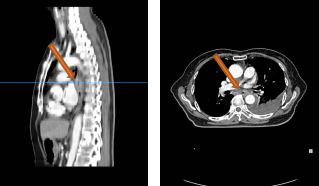

PET-CT(2020-08-13):食管胸下段管壁不均匀增厚,见放射性摄取增高,大小约18×14×27mm,SUVmax 14.6,符合食道癌表现。右侧肺门及纵隔(4R、5、7区)可见多个稍肿大淋巴结,最大约8×5mm,考虑炎性淋巴结可能性大。

左肺上叶尖后段团块状密度增高影,PET见放射性摄取增高,大小约40×29×31mm,SUVmax 28.0。病灶跨越左侧斜裂胸膜生长,密度均匀。左肺上叶胸膜下可见多发微小结节状密度增高影。建议治疗后复查,必要时活检排外恶性肿瘤的可能。

胸部平扫+增强CT(2020-08-27):食道中段管壁增厚,上下累及约4.5厘米(约胸5/6椎间隙水平至胸8椎体上缘水平),增强后可见轻度强化,隆突下见境界不清淋巴结。左肺上叶尖后段及相邻左肺下叶背段交界处见团块状直径约2.5厘米软组织密度灶,边缘可见毛刺,左侧胸腔积液,左下肺膨胀不全。右肺下叶见少许条状影。结论:1、食管癌。2、左肺上叶尖后段病灶,符合肺癌。左侧胸腔积液,左下肺膨胀不全。